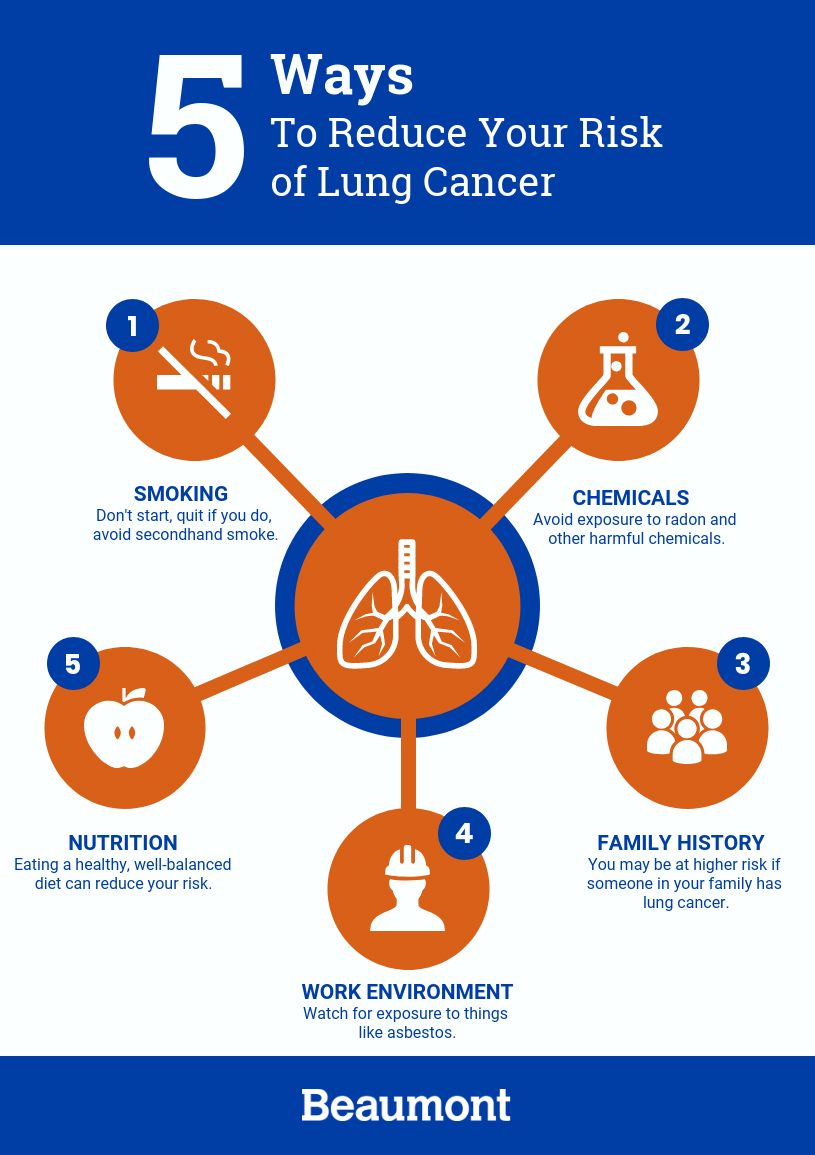

Reducing or eliminating occupational exposure to lung carcinogens. Screening is recommended if you’re at high risk. Smoke from other people’s cigarettes, cigars, or pipes is called secondhand smoke.

Avoiding things known to cause cancer. Learn what lung cancer is, what the symptoms are, how to lower your risk, and who should be screened for lung cancer. Advances in treatments have caused a.

Our dataset of 416 patients and over 1.6 million cells provided sufficient power to make predictions using artificial intelligence. Depending on the type of cancer and the stage, you may receive a. Reducing or eliminating exposure to radon.

Lung cancer is cancer that starts in your lungs. The most important thing you can do to prevent lung cancer is to not start smoking, or to quit if you smoke. Lung cancer patient and advocate jill feldman takes pills at home that shrink tumors by blocking a signal that tells cancer cells to grow.